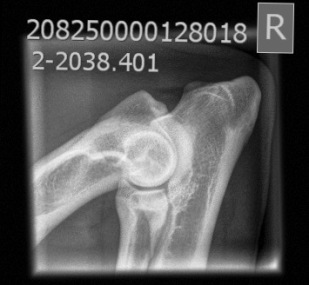

AD: 0/0